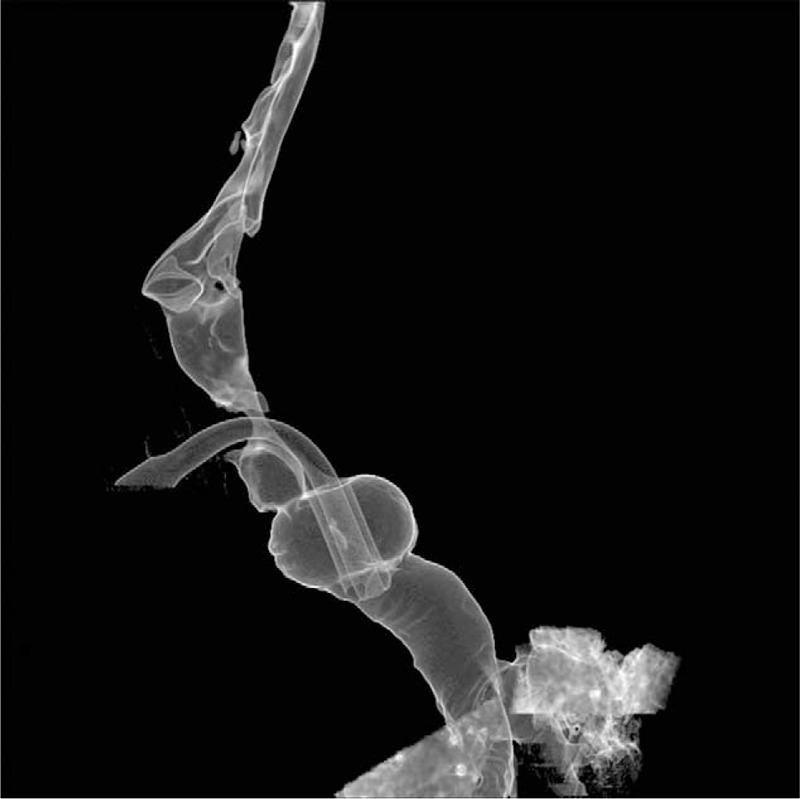

Tracheomegaly Secondary to Tracheotomy Tube Cuff in Amyotrophic Lateral Sclerosis: A Case Report.

Tracheomegaly has not been reported in amyotrophic lateral sclerosis (ALS). Herein, the authors report a case of tracheomegaly secondary to tracheotomy tube cuff in a patient with ALS. To our knowledge, this is the first report of an ALS patient with tracheomegaly and of tracheomegaly being associated with tracheotomy tube cuff and home tracheotomy mechanical ventilator.The clinician should consider the possibility of tracheomegaly in the differential diagnosis, if a patient with ALS develops repeat air leakage around the tracheotomy tube or rupture of tracheotomy tube cuff.